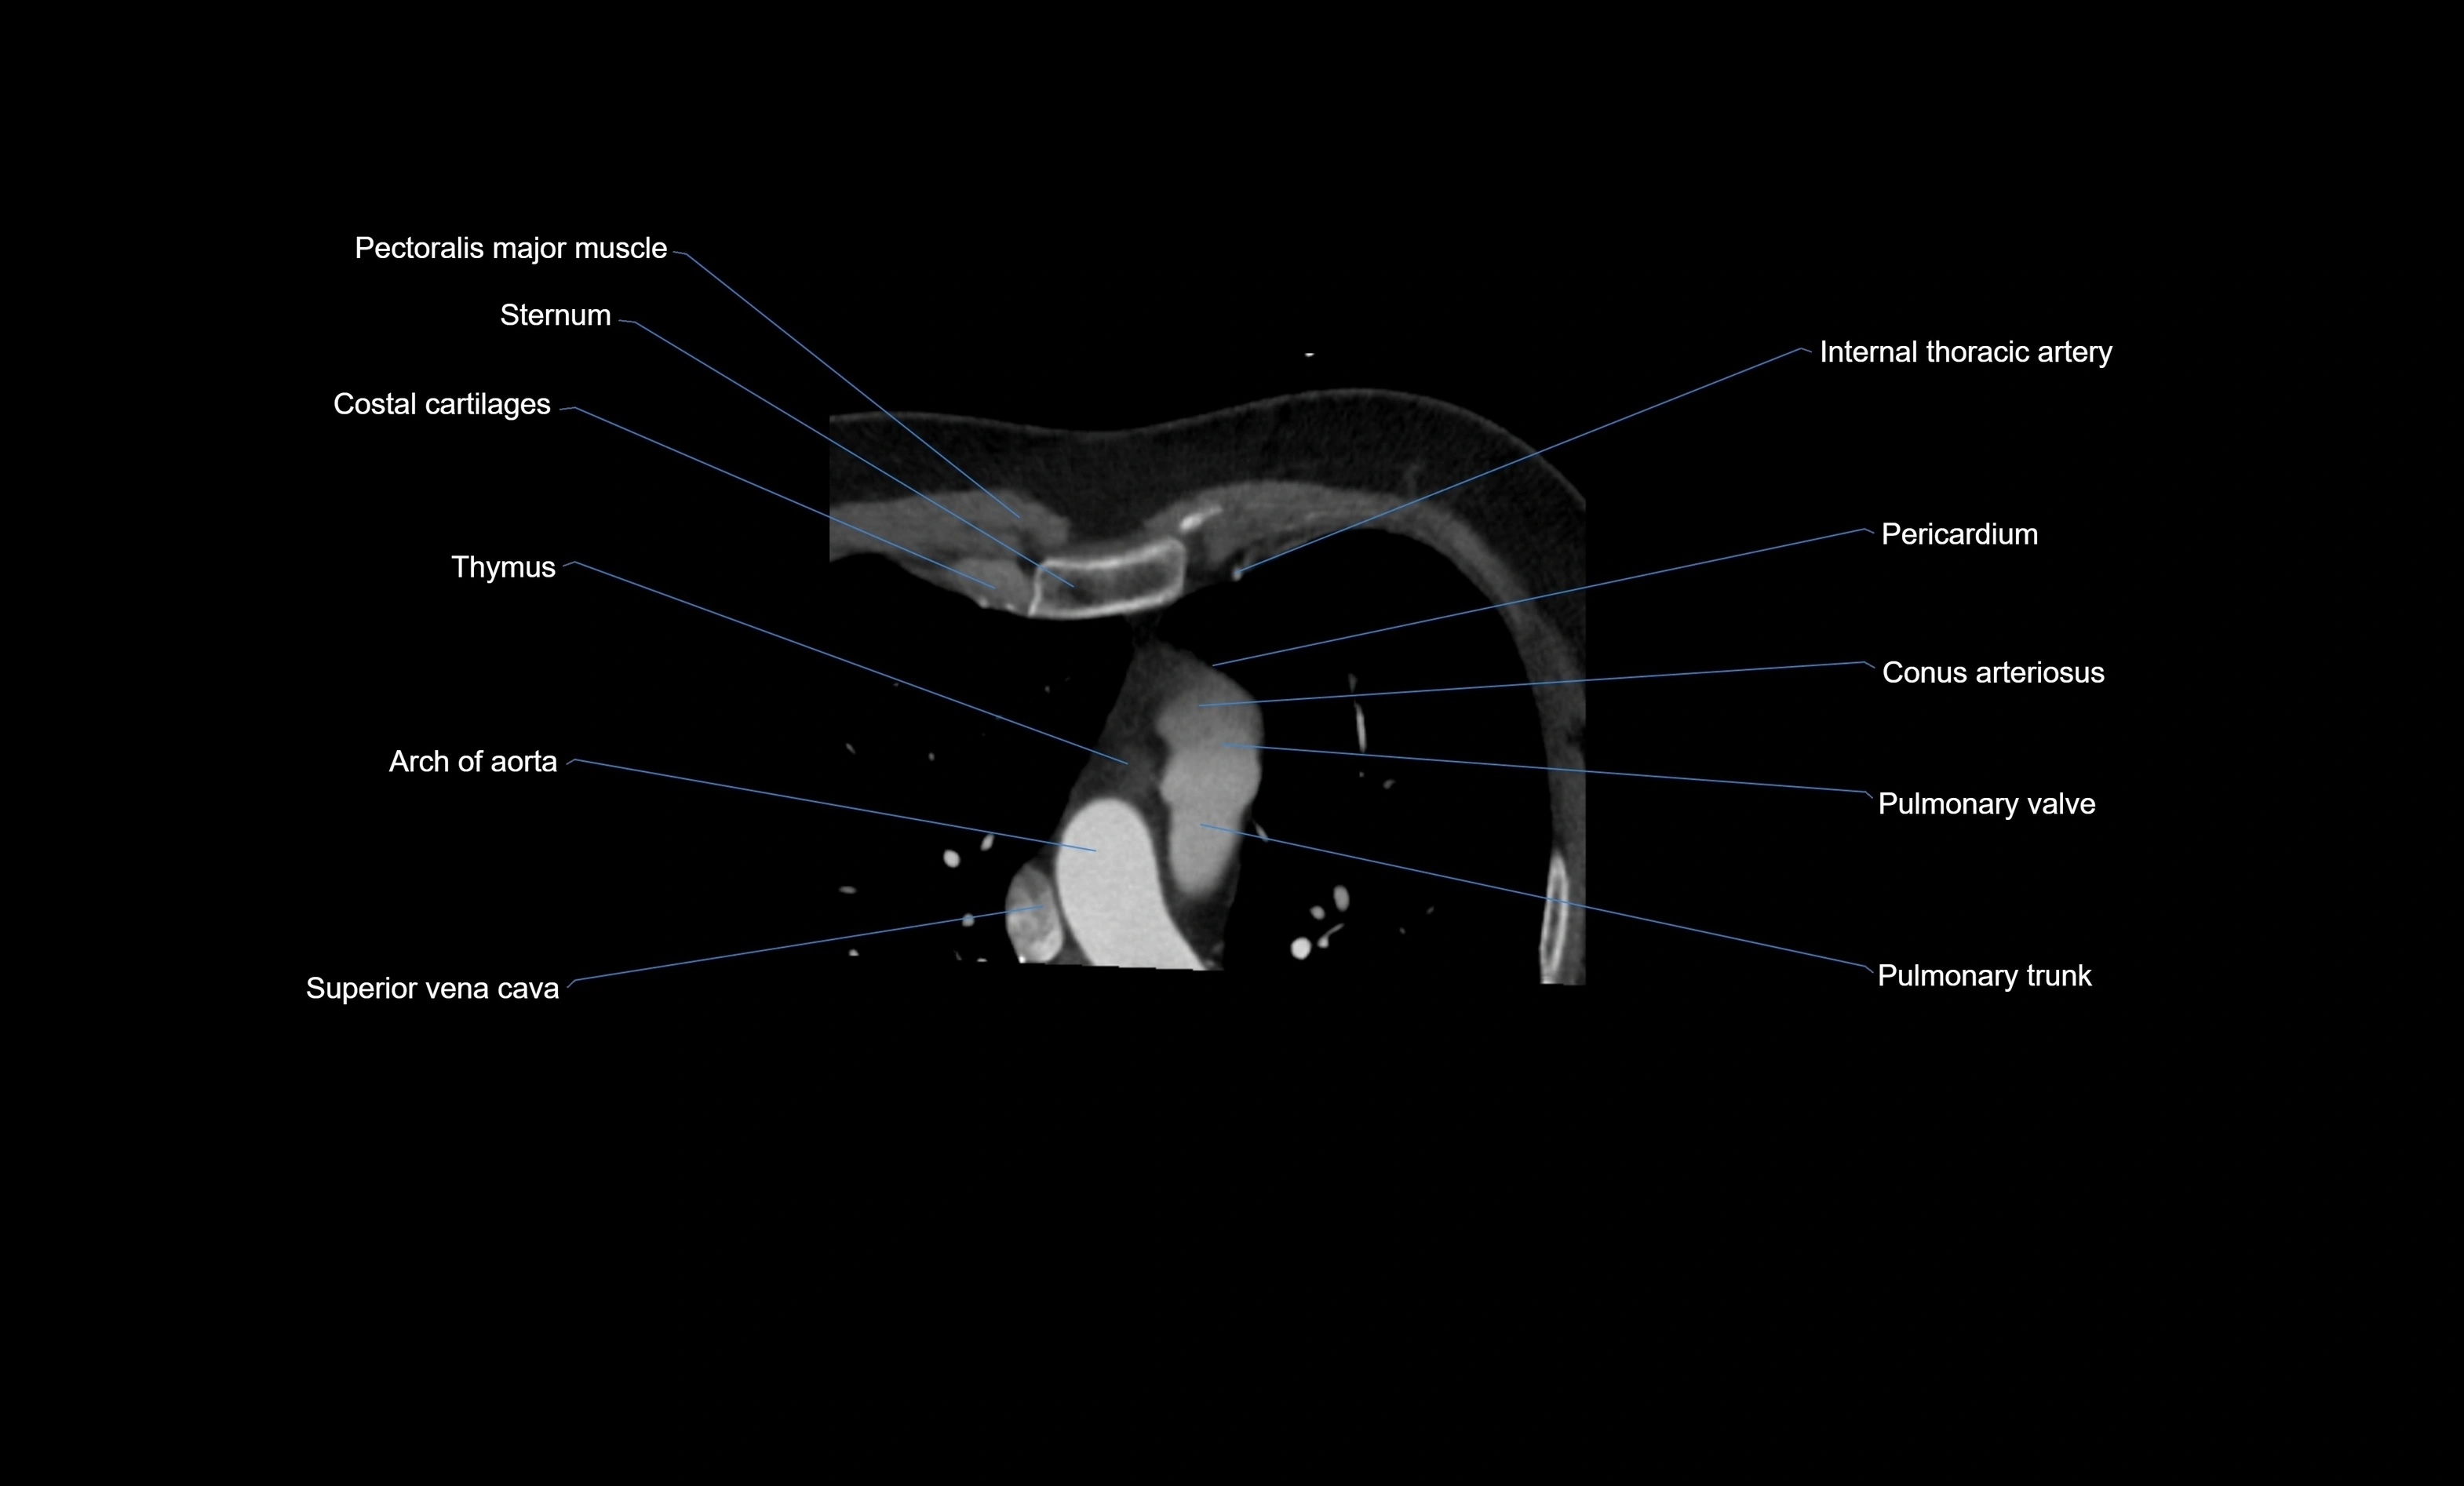

- Conus arteriosus

- Pulmonary trunk

- Pulmonary valve

- Pericardium

- Superior vena cava

- Arch of aorta

- Costal cartilages

- Sternum